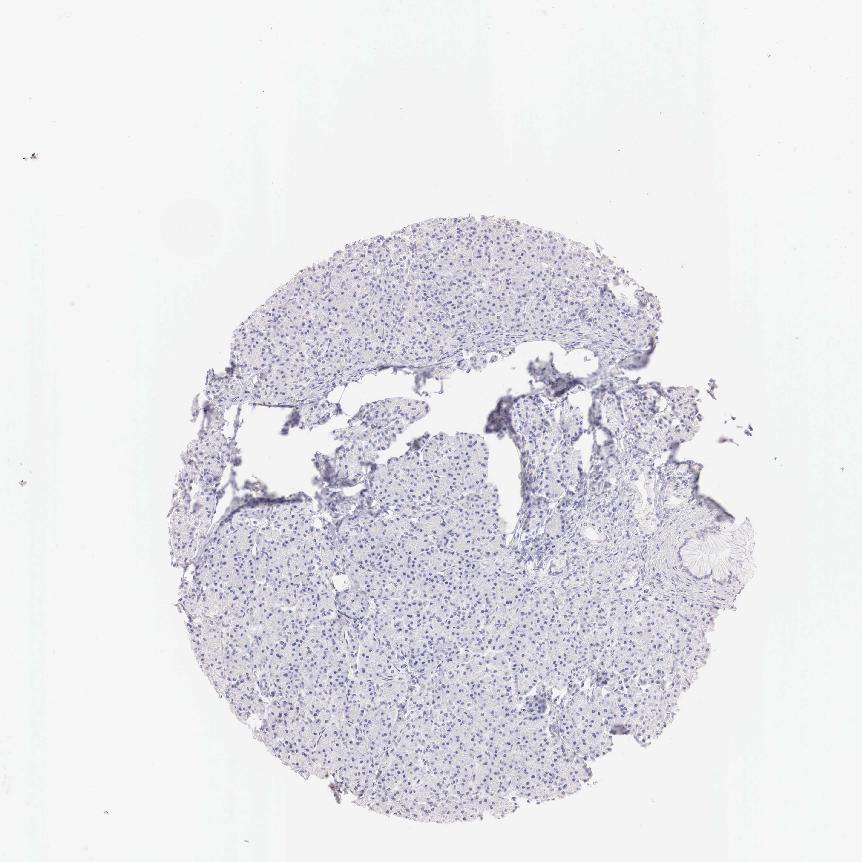

PANCREAS - Antibody stainingi

Antibody staining in the annotated cell types in the current human tissue is reported as not detected, low, medium, or high, based on conventional immunohistochemistry profiling in selected tissues. This score is based on the combination of the staining intensity and fraction of stained cells.

Each image is clickable and will lead to virtual microscopy that enables deeper exploration of all samples and also displays staining intensity scores, fraction scores and subcellular localization as well as patient and tissue information for each sample.

Antibody HPA001383Antibody CAB000043Antibody CAB020416Antibody CAB062555

Exocrine glandular cells MediumNot detectedNot detectedNot detected

Pancreatic endocrine cells LowNot detectedNot detectedNot detected